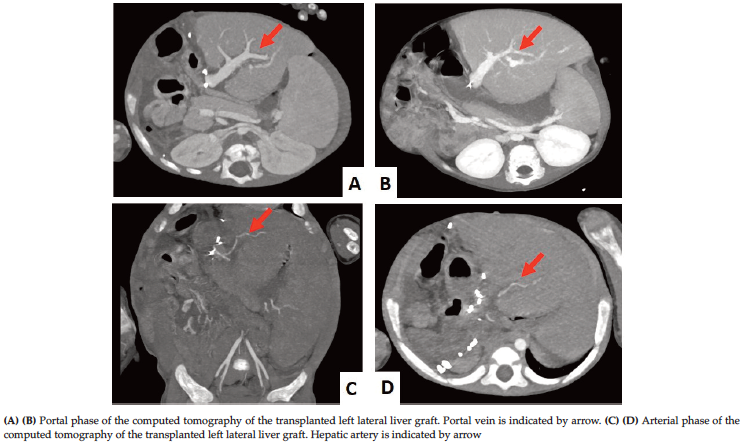

Eight of 9 LT recipients were children. All LTs were from living-related donors. Six of the recipients were male, and 3 of them were female. The most common indication for LT was biliary atresia (n = 4). The other etiologies were progressive familial intrahepatic cholestasis (n = 2), oxalosis (n = 1), tyrosinemia + hepatocellular carcinoma (HCC) (n = 1), and hepatitis B + HCC (n = 1). The mean age of children was 22 months (range, 3-96 months), and the adult recipient was 57 years old. The average weight of the recipients was 10.2 kg (range, 5-19 kg). The adult recipient’s weight was 74 kg. Demographics and clinical characteristics of LT recipients are summarized in Table 3. Five of the LT donors were mothers of recipients, 1 was a father, 1 was an uncle, 1 was an aunt, and 1 was a son. Seven of 8 liver grafts were left lateral segments, and 1 was a right segment. Abdominal CTs were performed on LT recipients on day 7 after surgery, and all results were normal (Figure 4). Mean serum total bilirubin values of the LT recipients were 0.9 mg/dL at post-operative day 7, 0.5 mg/dL at day 30, and 0.4 mg/dL at day 90 (Figure 5). Mean serum aspartate aminotransferase values of LT recipients were 38.1 U/L at postoperative day 7, 28.3 U/L at day 30, and 22.3 U/L at day 90 (Figure 6). The mean serum alanine aminotransferase values of recipients were 31.1 U/L at postoperative day 7, 23.7 U/L at day 30, and 15.2 U/L at day 90 (Figure 7). The average length of stay in the ICU was 3.4 days (range, 1-8 days). The average length of hospital stay was 17.1 days (range, 6-36 days). All LT recipients were discharged successfully. Only 1 liver recipient died (a pediatric patient), which was a result of oxalosis-induced heart failure 55 days after LT. He was discharged on day 26 after LT. Sixteen days after discharge, he returned to the hospital with heart failure and died on day 13 after admission.